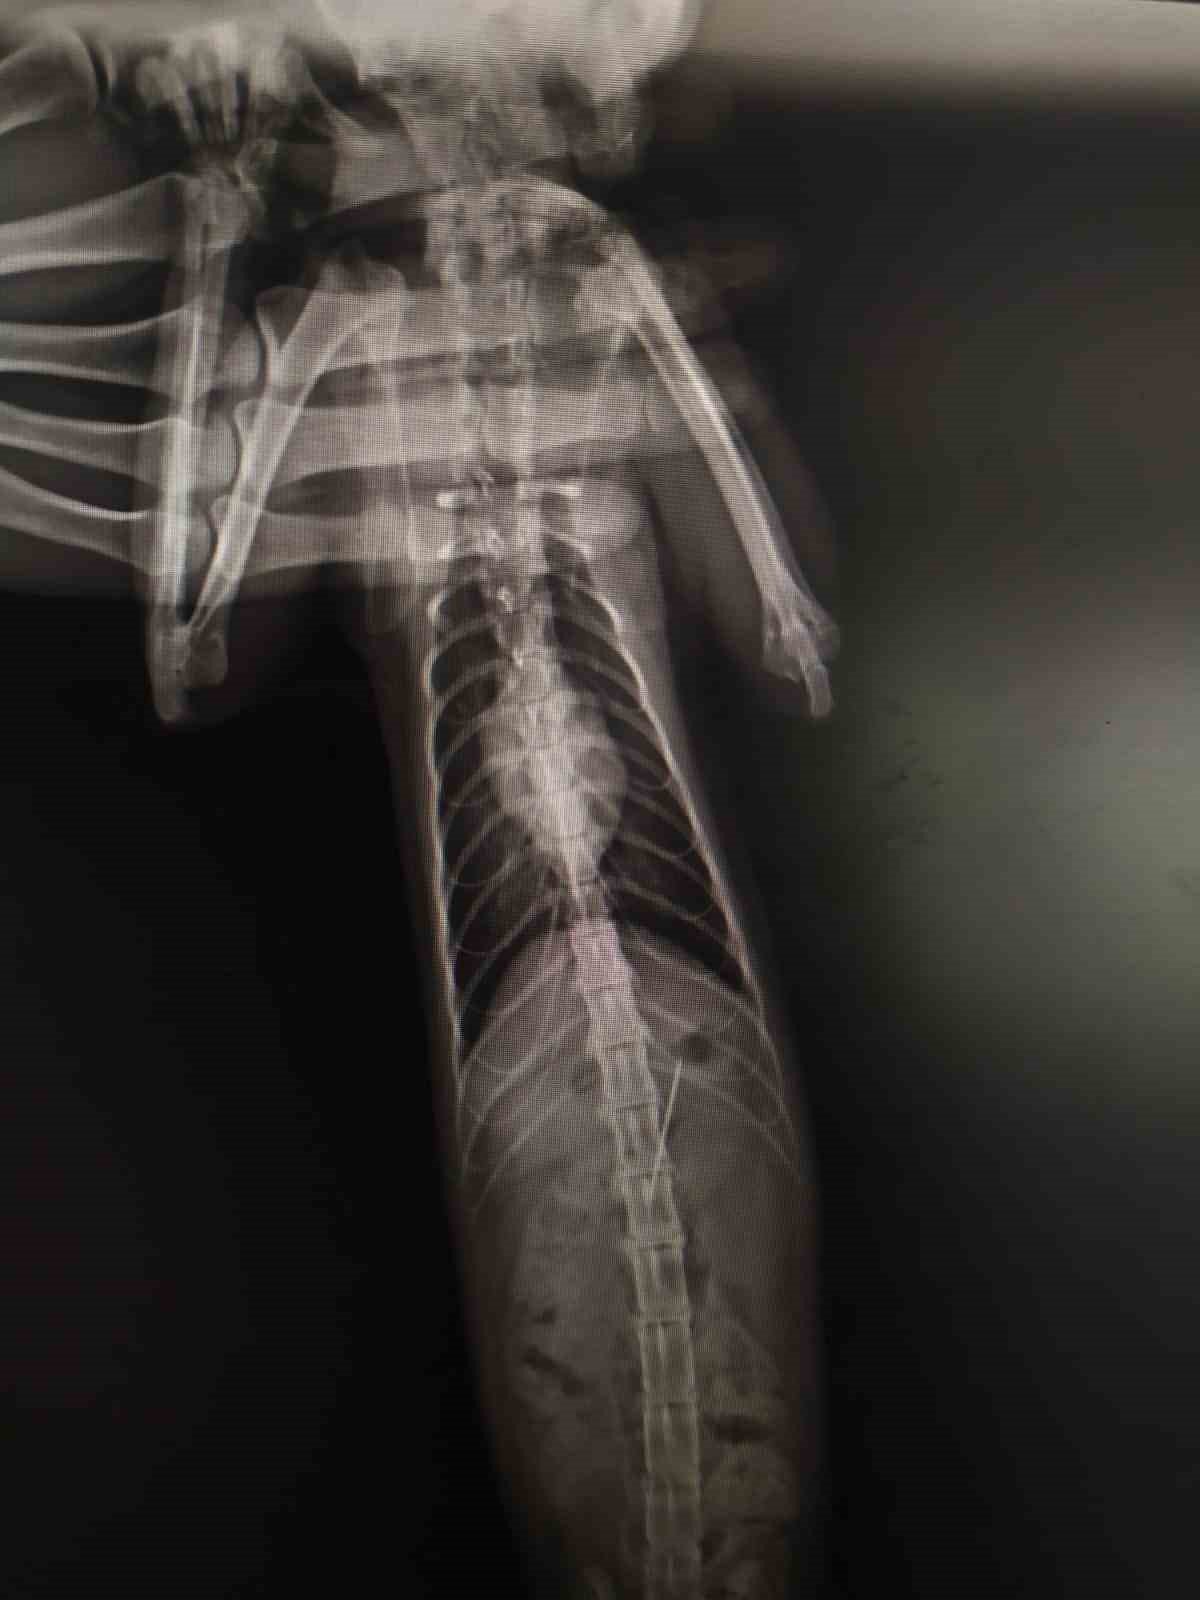

Bolu'da kedisinin rahatsızlandığını fark eden bir kişi veteriner hekime başvurdu. Edinilen bilgiye göre, özel bir veteriner kliniğinde muayene edilen kedinin röntgeni çekildi. Kedinin midesinde dikiş iğnesi olduğu görüldü. Endoskopiyle dikiş iğnesi kedinin midesinden çıkartıldı. Bir süre veteriner kliniğinde müşahede altında tutulan kedi taburcu edildi.

Kedinin dikiş iğnesin yuttuğu öne sürüldü.